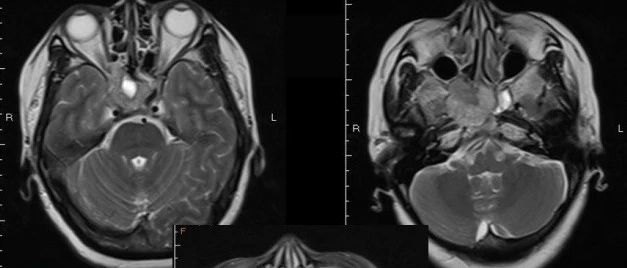

西班牙塞维利亚Virgendel del Rocío大学医院神经外科的Eugenio Cárdenas Ruiz-Valdepeñas等报告1例内镜下经鼻入路切除斜坡脊索瘤时损伤基底动脉案例。文章发表于2021年2月《Operative Neurosurgery》杂志。——摘自文章章节长按识别二维码查看原文【Ref: Cárdenas Ruiz-Valdepeñas E, et al. Oper Neurosurg (Hagerstown). 2021 Feb 16;20(3):282-288. doi: 10.1093/ons/opaa367.】...